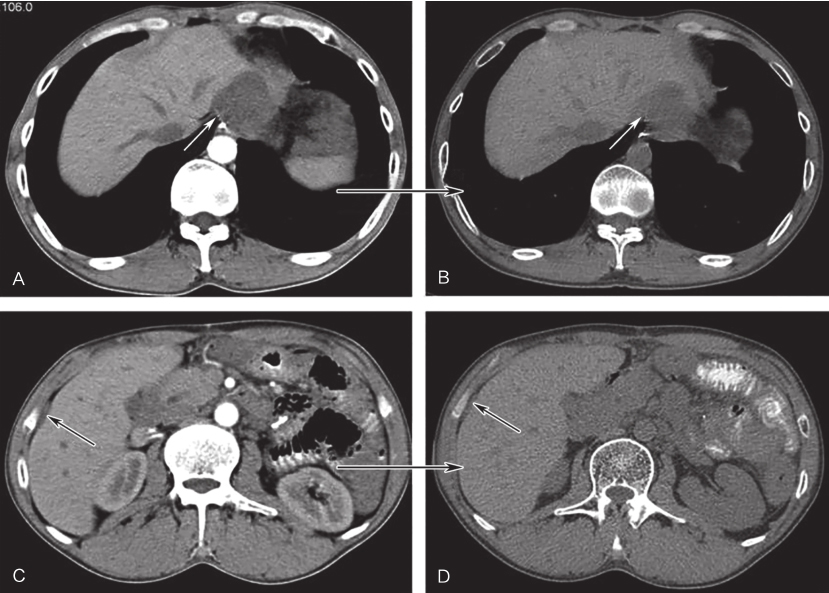

钟碧慧、陈旻湖:肝大的诊断步骤和常见原因

1小时条评论肝大从形态上可分为弥漫性肿大和局部占位两大类。病因繁多,临床诊断时可先初步区分为感染性与非感染性疾病。根据突出的伴随症状或体征选择合理的实验室检查和影像学检查,逐步缩小鉴别范围,必要时行组织学检查...